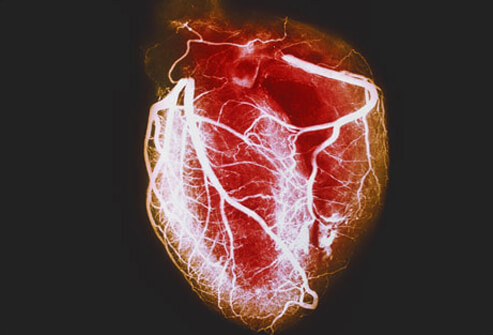

Valor de la ausencia de calcio coronario para descartar obstrucción significativa

Un puntaje de 0 en el calcio coronario medido por angiotomografía computada reduce sustancialmente el riesgo de enfermedad coronaria en los adultos mayores, pero en los pacientes más jóvenes se halló que una proporción considerable de la coronariopatía obstructiva ocurre en aquellos sin calcio coronario. JAMA Cardiology, 27 de octubre de 2021.